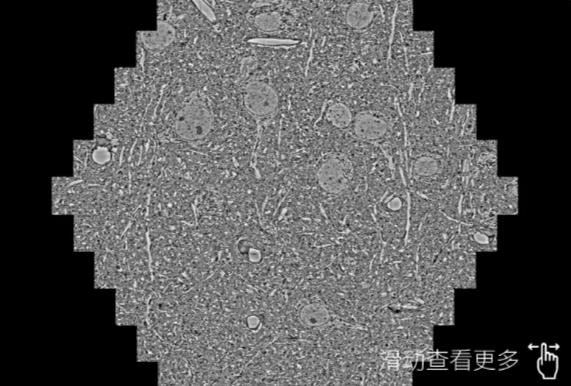

鼠脑切片。左图使用张家界蔡司张家界扫描电镜MultiSEM706对165μmx143pm面积区域成像,耗时仅需1.5秒。右图为鼠脑切片中30μm区域放大效果。样品由芝加哥大学B.Kasthuri提供。

使用蔡司高速张家界扫描电镜MultiSEM对1mm²人脑皮层组织进行高分辨成像,并对其中的各种细胞结构进行三维重构分析。左图展示了2x3mm²组织平面中锥体神经元的三维重构效果。右图显示了局部体积神经元三维重构。图像由哈佛大学chtman实验室提供,渲染图由D. Berger 制作。